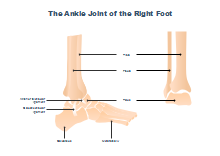

illustrazione scientifica - anatomia umana